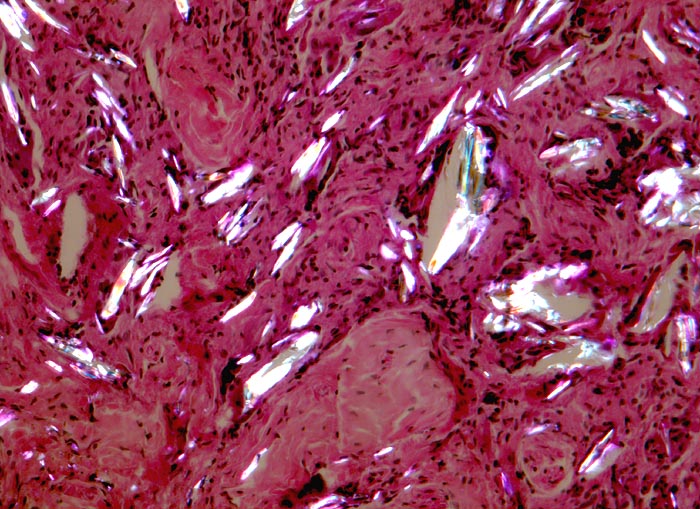

Histologisch besteht das Granulom aus Makrophagen, welche sich zu grossen Zellen mit unscharfen Zellgrenzen, den Epitheloidzellen differenziert haben. Einige der Epitheloidzellen können zu Riesenzellen vom Fremdkörpertyp fusionieren, welche oft phagozytiertes Material enthalten. Im Gegensatz zu den T-Zell induzierten Riesenzellen vom Langhans Typ mit hufeisenartig in der Peripherie angeordneten Kernen, sind die Kerne der Fremdkörperriesenzellen zufällig im Zytoplasma verteilt.

Morphologische Merkmale:

• Knotige Granulome umgeben von wenig Skelettmuskulatur.

• Granulombildung aus Histiozyten und mehrkernigen Riesenzellen vom Fremdkörpertyp.

• Im Zytoplasma der Riesenzellen findet sich phagozytiertes exogenes Fremdmaterial.

• In den helleren Arealen des Granuloms liegen grössere Ansammlungen von Fremdmaterial extrazellulär.